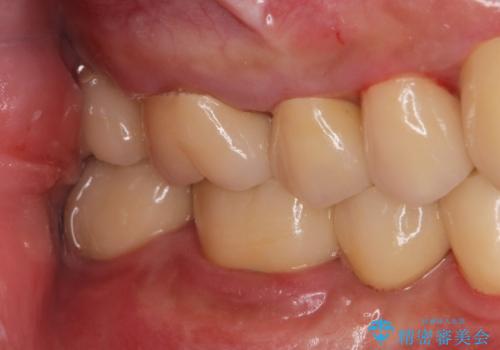

その後、インプラント治療、セラミック治療を行いました。

一度治療するはを全て仮歯に変えて、歯茎を整えてからセラミックを装着しました。

適合の良い被せ物、インプラントが入りました。